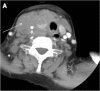

Focal and diffuse thyroid abnormalities are commonly encountered during the interpretation of computed tomography (CT) exams performed for various clinical purposes. These findings can often lead to a diagnostic dilemma, as the CT reflects the nonspecific appearances. Ultrasound (US) examination has a superior spatial resolution and is considered the modality of choice for thyroid evaluation. Nevertheless, CT detects incidental thyroid nodules (ITNs) and plays an important role in the evaluation of thyroid cancer. In this pictorial review, we cover a wide spectrum of common and uncommon, incidental and non-incidental thyroid findings from CT scans. We also discuss the most common incidental thyroid findings, best practices for their evaluation, and recommendations for their management. In addition, we explore the role of imaging in the assessment of thyroid carcinoma (before and after treatment) and preoperative thyroid goiter, as well as localization of ectopic and congenital thyroid tissue.

Teaching points: • Thyroid disorders tend to have non-specific CT appearances. • ITNs are common on neck CT. • ITN management depends on nodule size, age, health status, lymphadenopathy, and invasion. • CT is used in assessment of cancer extension, mass effect, invasion, and recurrence. • CT plays a role in preoperative planning in patients with symptomatic goiter.